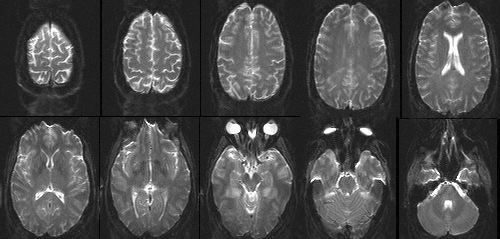

If you collect this light, using fancy mathemagics, you can plot relaxation time across the brain!

high spatial resolution: ~1 mm

this is measured using the receiver head coil

- high-resolution (1 mm)

- "anatomical scan"

- T1-weighted image

[x, y, z]

- low-resolution (1 mm)

- "functional scans"

- EPI images

- measured over time

[x, y, z, t]